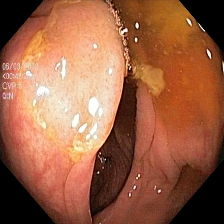

To show the effectiveness of our decoder consistency training approach, we compared our model with and without our consistency training approach. Table 2 shows the results of our model’s performance with and without consistency training. Using our consistency training approach, we are able to reduce false positive rates and improve the segmentation results for Kvasir-SEG [7], ClinicDB [1], ETIS [10], and EndoScene [13] datasets. Sample segmentation results as seen in Figure 2 also support these improvements.

Figure 2: Sample segmentation results of the benchmark models compared with PlutoNet without (Plu nC) and with consistency training (Plu wC). Images shown in the first column belong to Kvasir, ClinicDB, ColonDB, EndoScene, and Etis datasets.